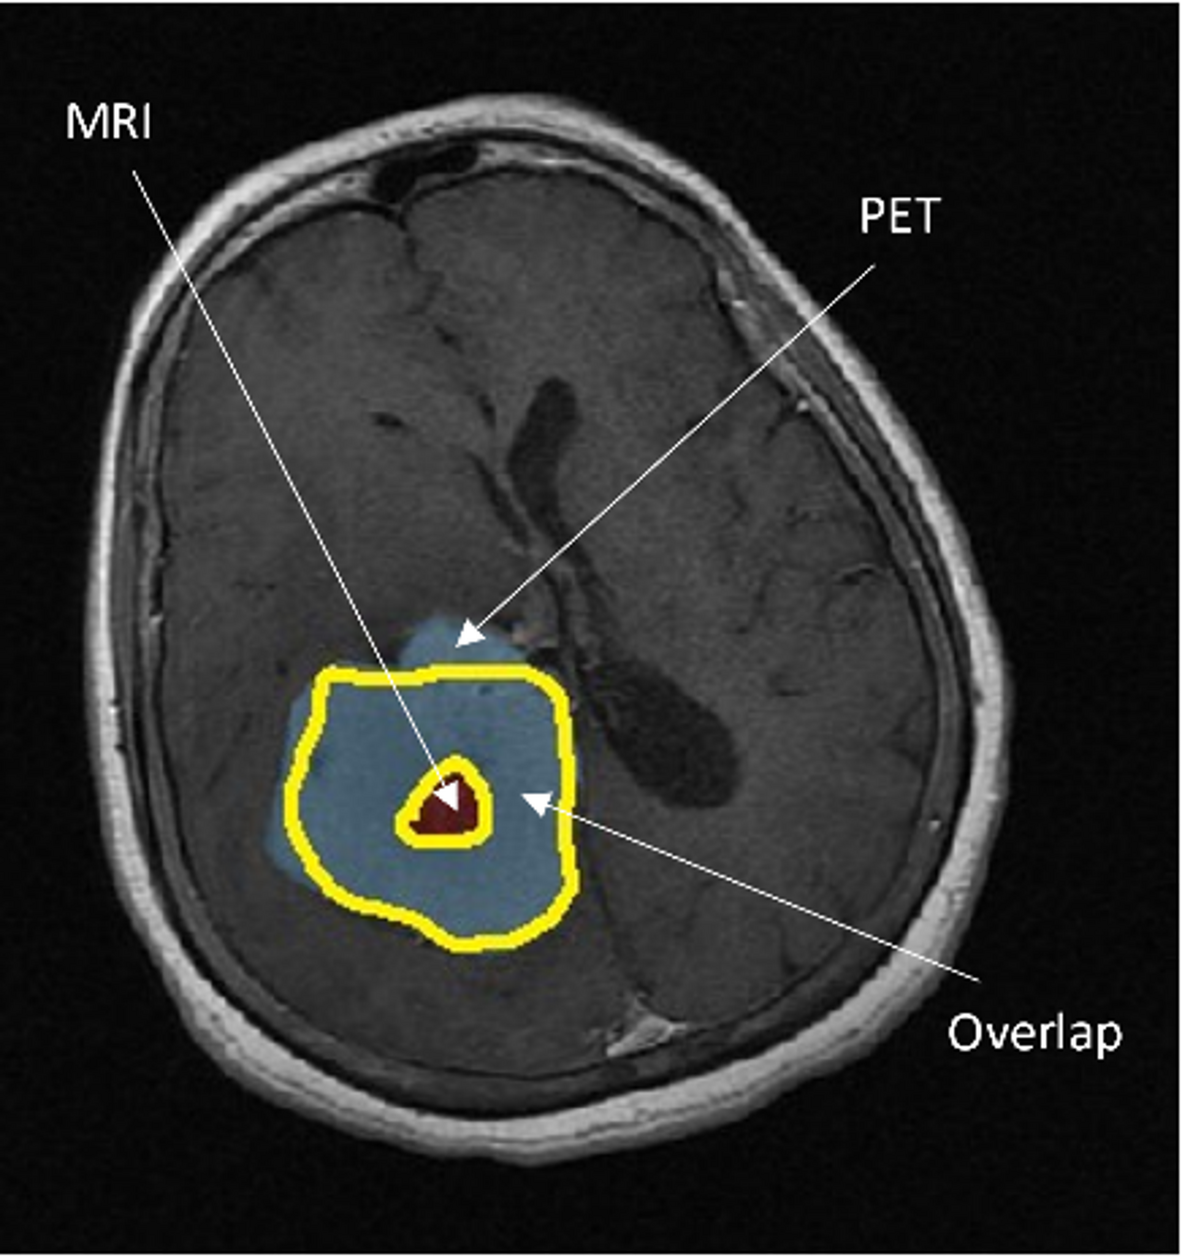

Fig. 7

Axial slice of the brain obtained using contrast-enhanced MR, showing PET and MRI-derived tumor volumes: Voverlap, VonlyPET, and VonlyMR.